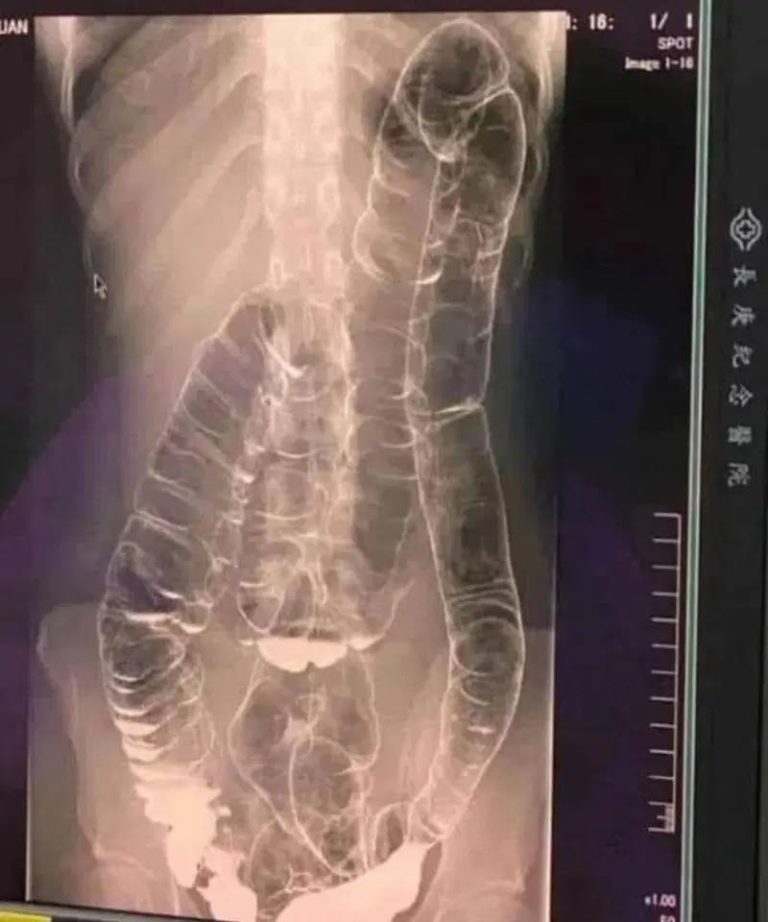

A saturated colon: when the body sounds the alarm

A saturated colon: when the body sounds the alarm   Who hasn’t encountered constipation? This problem, often perceived as trivial, can transform into a real nightmare if it becomes constant. This is exactly what occured to a young woman whose overloaded colon ended up dangerously dilating. So, how can we prevent this digestive disorder from … Read more